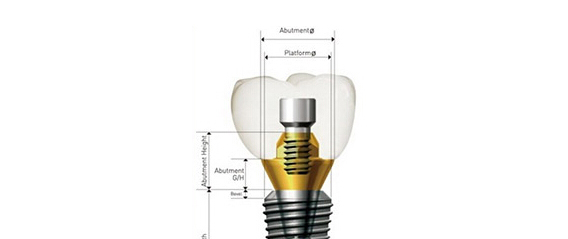

数字化种植是利用计算机图形图像技术,根据口内CT扫描数据以及光学扫描数据在计算机上重建患者颌骨立体模型,医生以此为基础,确定患者种植体嵌入位置、数量、种植深度、角度等,生成科学、精准的导板设计方案,将种植设计准确地转化到手术操作中,最后配上数字化种牙手术专用的手术工具、结合患者自身的情况制作修复体,完成种植治疗。

- 口内模拟种植,避开神经血管,设计种植方案;通过CAD/CAM激光扫描和CBCT检测等, 在计算机上重建患者口腔三维立体模型,凭借由打印技术制作的种植导板对手术全程的精准把控,减少手术时间及手术创伤,实现对缺牙的修复。

- 导板技术就犹如地图,精准的为医生指引着方向,精确到 0.1毫米。

- 利用数字化技术,术前充分评估患者条件,设计合适的种植体数量、型号和具体位置,保证负重的成功及植体稳定性,配合使用打印种植导板精确实现设计的种植方案,同时缩短手术时间,减少手术创伤,让患者有更好的体验。

在导板辅助下可避免医生经验误差,掌控种植角度和深度,减少创伤,有效避开神经、血管等危险部位。